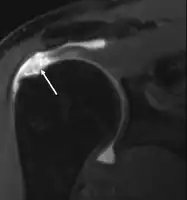

MRI

Magnetic resonance imaging (MRI) and ultrasound[46] are comparable in efficacy and helpful in diagnosis, although both have a false positive rate of 15–20%.[47] MRI can reliably detect most full-thickness tears, although very small pinpoint tears may be missed. In such situations, an MRI combined with an injection of contrast material, an MR-arthrogram, may help to confirm the diagnosis. It should be realized that a normal MRI cannot fully rule out a small tear (a false negative) while partial-thickness tears are not as reliably detected.[48] While MRI is sensitive in identifying tendon degeneration (tendinopathy), it may not reliably distinguish between a degenerative tendon and a partially torn tendon. Again, magnetic resonance arthrography can improve the differentiation.[48] An overall sensitivity of 91% (9% false negative rate) has been reported, indicating that magnetic resonance arthrography is reliable in the detection of partial-thickness rotator cuff tears.[48] However, its routine use is not advised, since it involves entering the joint with a needle, with the potential risk of infection. Consequently, the test is reserved for cases in which the diagnosis remains unclear.